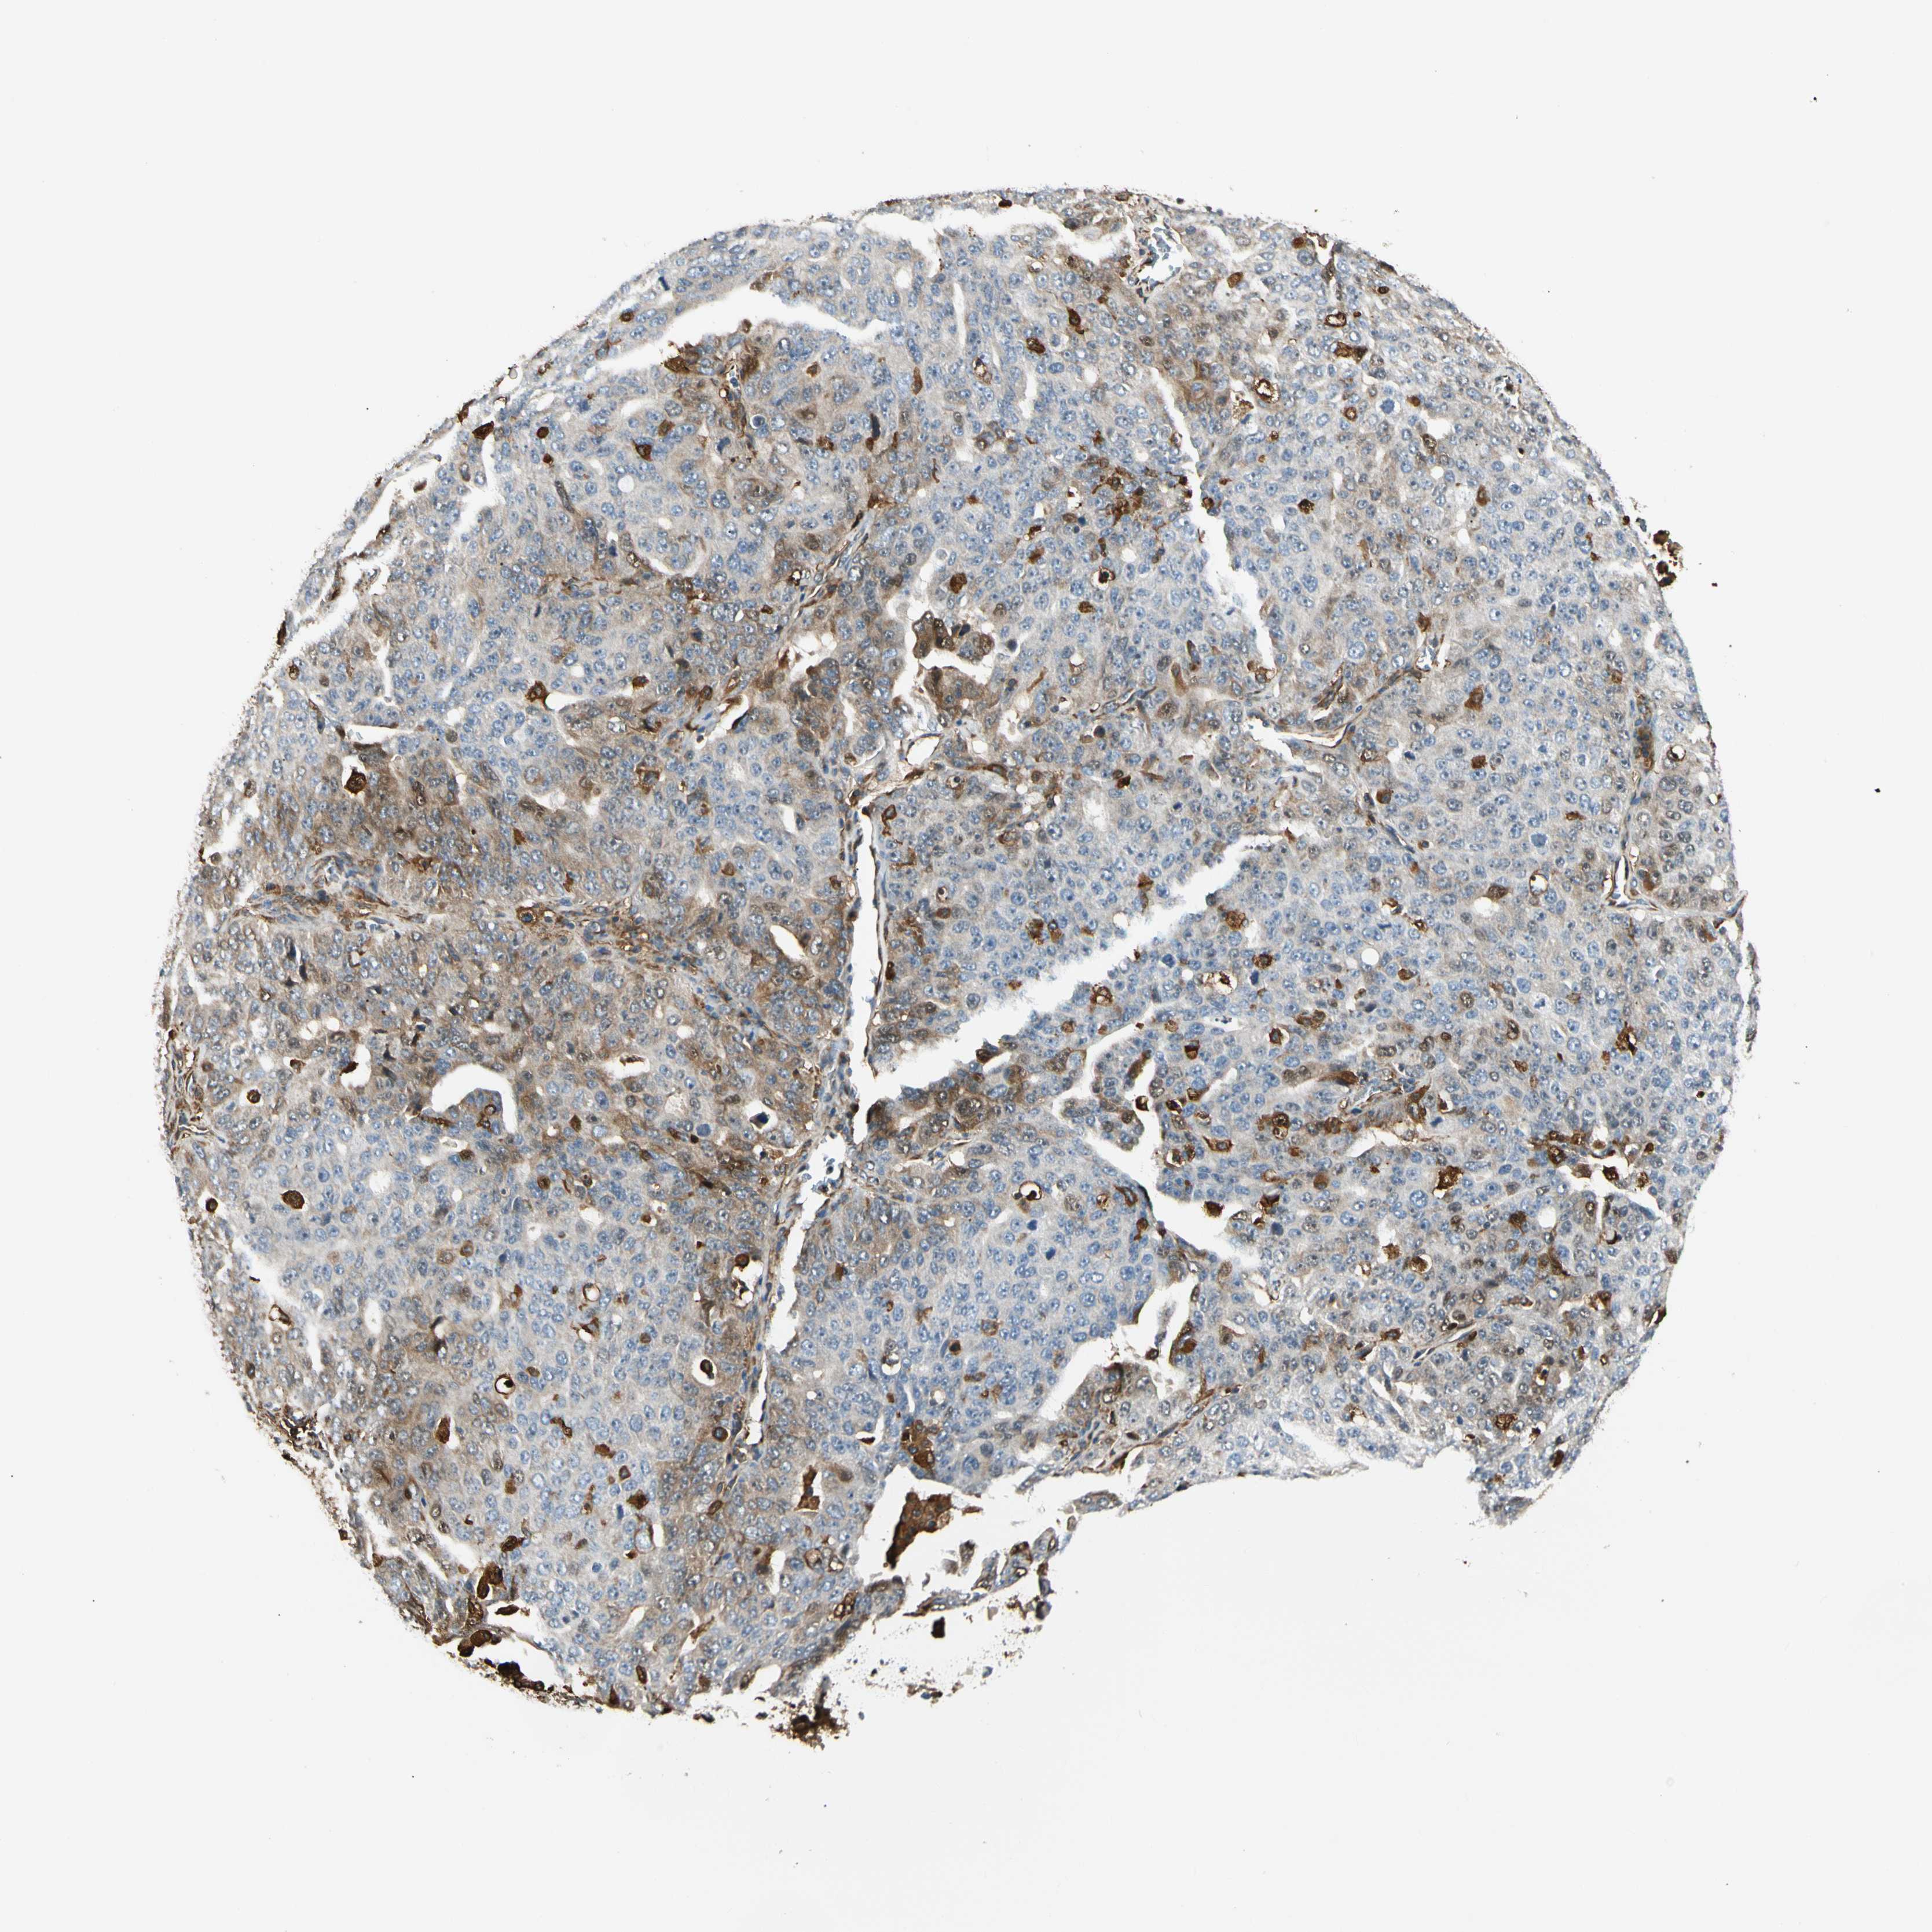

OVARIAN CANCER - Protein expressioni

A mouse-over function shows sample information and annotation data. Click on an image to view it in a full screen mode. Samples can be filtered based on level of antibody staining by selecting one or several of the following categories: high, medium, low and not detected. The assay and annotation is described here.

Note that samples used for immunohistochemistry by the Human Protein Atlas do not correspond to samples in the TCGA dataset.

Antibody stainingi

Antibody staining in the annotated cell types in the current human tissue is reported as not detected, low, medium, or high, based on conventional immunohistochemistry profiling in selected tissues. This score is based on the combination of the staining intensity and fraction of stained cells.

Each image is clickable and will lead to virtual microscopy that enables deeper exploration of all samples and also displays staining intensity scores, fraction scores and subcellular localization as well as patient and tissue information for each sample.

Antibody CAB008623

Staining

High

Medium

Low

Not detected

Intensity

Strong

Moderate

Weak

Negative

Quantity

>75%

75%-25%

<25%

None

Location

Nuclear

Cytoplasmic/membranous

Cytoplasmic/membranous,nuclear

Cystadenocarcinoma, serous, NOS

Carcinoma, endometroid

Cystadenocarcinoma, mucinous, NOS

Carcinoma, NOS